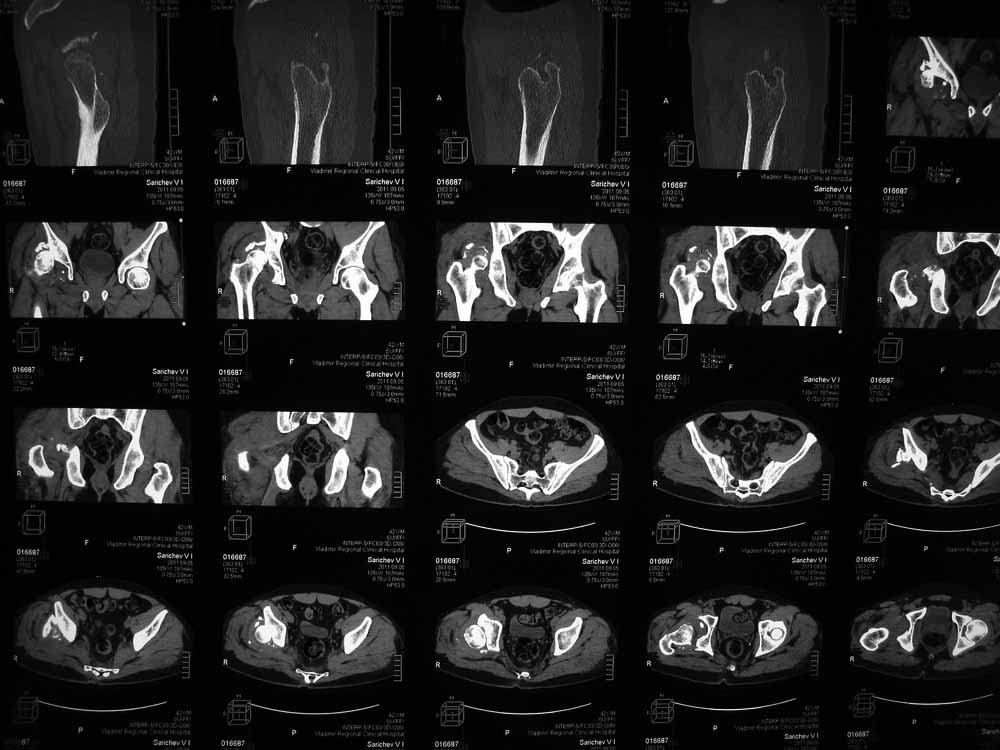

Вот еще сканы.

В этой ситуации предпочел бы эндопротез, шансы на жизнеспособность головки в таком сроке вывиха исчезающе малы, попытка синтезировать задний край в этих же сроках (ретракция мышц, рубцы) скорее всего приведут к его девитализации с последующим аваскулярным некрозом. Выбор вертлужного компонента проще планировать после 3D, скорее всего можно будет обойтись стандартными предложением, возможно, с котилопластикой.